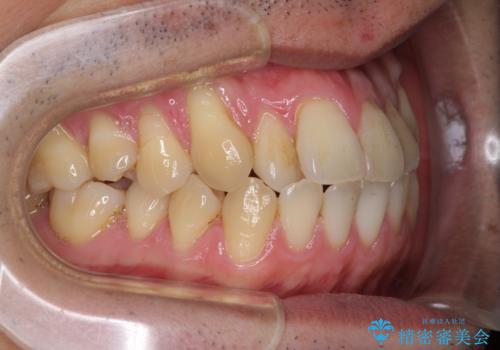

八重歯の歯根が見えている点も気になっているので、矯正歯科治療後に歯肉移植による根面被覆を行うこととしました。

また、ワイヤー矯正と異なり歯軸改善の強い力を前歯にかけるため、反対咬合で裏側にある歯の歯肉が退縮しやすくなります。

矯正治療により元々気になっていた八重歯と、反対咬合が改善された歯の2本に対して根面被覆を行い、審美面の改善も達成しました。